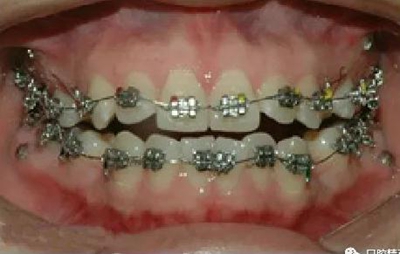

微型種植釘直徑僅有1.6mm和2mm,植入部位幾乎可以不受限制,可植入牙槽骨的任何部位,微型種植體支抗植入手術(shù)操作簡(jiǎn)單、安全,不需要牙齦翻瓣,即可旋入微型種植體,整個(gè)手術(shù)過(guò)程僅需5-10min,術(shù)后患者的不良反應(yīng)少,微型種植體的取出亦非常簡(jiǎn)單,甚至不需局部麻醉,將其反向旋出即可。自攻型種植釘植入牙槽骨中起支抗作用.

一般情況下是成年人使用,特殊病例十三、四歲的小孩可以用。種植釘可以打在牙槽骨的任何部位??梢栽?個(gè)牙齒之間的牙槽骨上打釘,或者打在頰側(cè)牙槽骨與牙根之間,主要看你是如何應(yīng)用支抗了。2個(gè)牙齒之間的牙槽骨上打釘,支抗作用拉動(dòng)的牙齒有限,而打在頰側(cè)牙槽骨與牙根之間可以將整個(gè)牙列拉向遠(yuǎn)中移動(dòng)。種植支抗釘在矯正結(jié)束后要拿下來(lái)。

2、助攻型種植釘,上頜與頜骨成30-40°角,下頜與頜骨成10-20°角(目的:1、降低損傷牙根及牙周膜的機(jī)率;2、使種植釘盡量植入骨皮質(zhì)內(nèi),降低松動(dòng)機(jī)率);自攻型種植釘與頜骨垂直;個(gè)人習(xí)慣:自攻型種植釘上下頜均與頜骨成30-40°角。